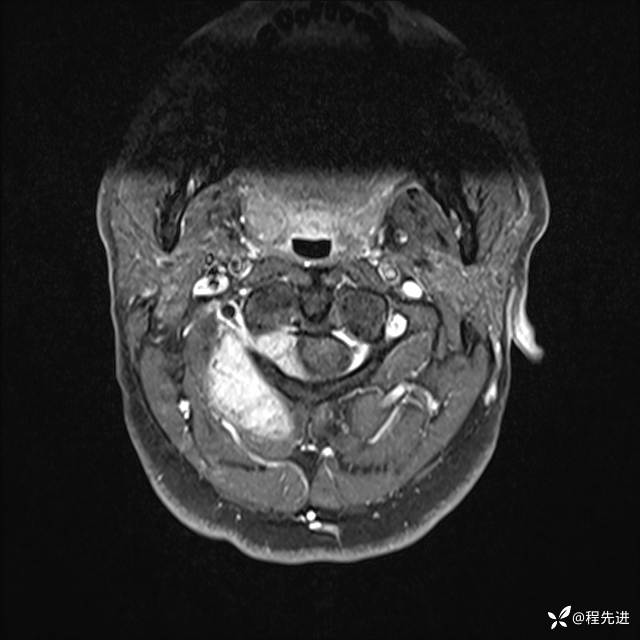

MRI平扫+增强:

T1增强: